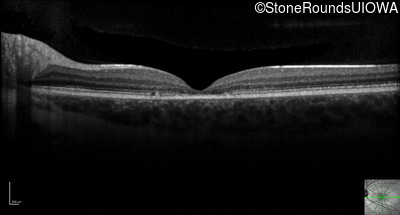

Optical Coherence Tomography - Right - 20/32

Exemplar / OCT Stack

Optical Coherence Tomography - Left - 20/50